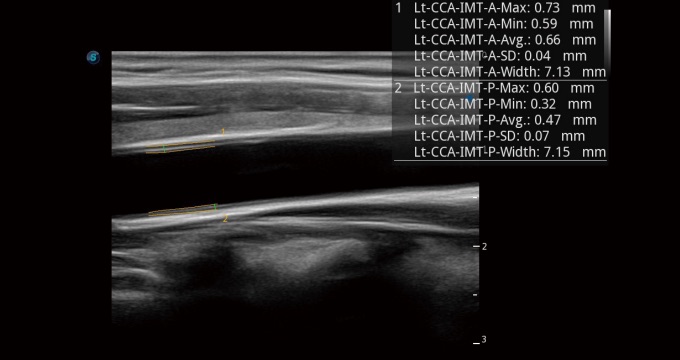

• 血管内中膜自动测量 Auto IMT

血管内中膜的厚度值是预测心血管疾病风险的重要指标,Auto IMT可以实现血管近场和远场内中膜厚度的自动测量,为临床提供快捷有效的诊断工具。